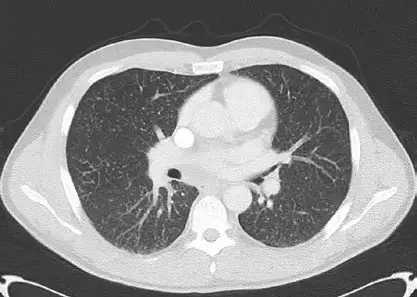

比如体检发现了肺部微小结节,如果长期随访观察都没有任何变化,或者甚至有缩小,那么一般考虑是良性的结节;而如果在随访过程中结节出现了增大,或者结节实性成分出现了增多,那么这个时候就要考虑是恶性的可能了。而如果怀疑是恶性,那么需要立即进行手术切除治疗。对于早期的肺癌,手术切除一般都可以取得非常不错的治疗效果。

左上肺部磨玻璃结节(早期肺癌)

总结:对于老百姓说的双肺多发微小结节的原因,比较常见的就是以上几种原因,除此之外还有最近出现的双肺多发肺部磨玻璃结节,尤其需要密切随访,定期观察,一旦出现恶性倾向,及时手术治疗,这才是上上之策